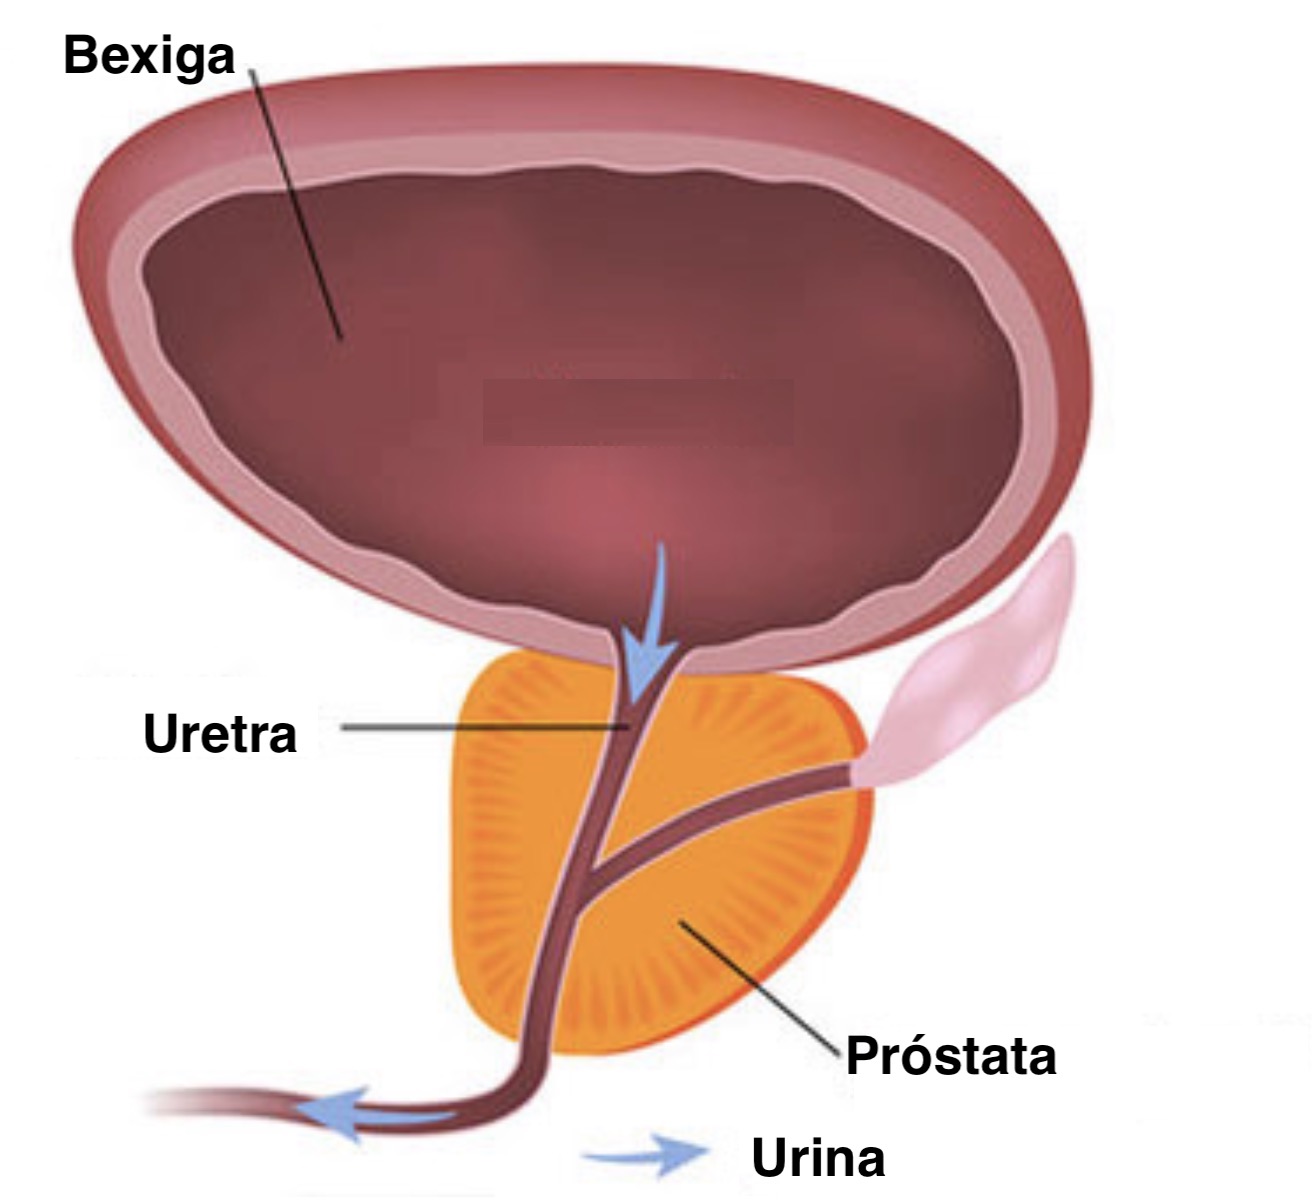

Простата, обычно ассоциируемая с мужским здоровьем после полового созревания, также присутствует у детей, хотя и в значительно меньших размерах. Этот орган, расположенный под мочевым пузырем и окружающий уретру, играет роль в выработке жидкости, которая составляет часть семенной жидкости. Несмотря на то, что проблемы с простатой у детей встречаются редко, понимание её развития и потенциальных патологий важно для ранней диагностики и лечения.